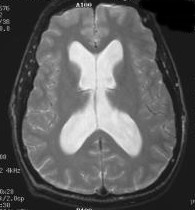

Below, are my CT images beginning on Jan. 17, 2011, where there is some enlargement of the ventricles, followed by further enlargement on April 9, 2011, even more enlargement on June 8, 2011, despite my May 23, 2011 revision. Finally, there was slight reversal of ventricular enlargement on June 20, 2011, and then normal sized (almost too small) ventricles on July 23, 2011. In hindsight, one mis-step my neurosurgeon and I made in this was in not doing a CT scan right before surgery so as to have a true baseline. My headache, nausea, memory, and balance symptoms had worsened from April 9, 2011 to May 23, 2011, and I had lost appetite and weight. A CT on the revision date would have likely shown considerably more ventricular enlargement compared to April 9th, rendering the post op CT of June 8, 2011 an improvement instead of a worsening as we believed. I was having ongoing headaches upon waking in the a.m. and during the daytime with the proGAV revision, no real improvement in memory, and no apparent improvement on CT compared to April 9th, I requested the proGAV to be lowered all the way to 0 during only a few weeks post op. Despite programmable shunts having been in use today for 12 years, there remains some considerable confusion and miscalculations in achieving optimal shunt settings. I remain dissatisfied with industry's inattentiveness to this issue, and I think this lack of attentiveness also speaks to the high number of unofficial reports of accidental reprogramming of (Codman & Medtronic) programmable shunts. Of course, with the proGAV's addition of a locking pin on the GAV valve wheel, it is unlikely it will succumb to any accidental reprogramming.

Under each of my CT images, I list the proGAV's corresponding setting. It was initially set at 10 during surgery. Then with no improvement in my complaints one week later, I asked that it be lowered to 7, and one week later to 5, then to 3, and finally to 0. During this period, almost every morning I awoke with a substantial headache that I assumed was due to increased ICP and underdrainage. On the June 20, 2011, CT we could finally see some decrease in the dilation of my ventricles, and determined the shunt to be working. But, we were still puzzled by the ongoing awaking a.m. headaches. For this reason, it was temporarily raised to a setting of 2, and then with no relief back down to 0. It remained at 0 for almost a month when the July 23, 2011 scan revealed normal sized ventricles.  Because of the relatively short period it took for my ventricles to come down to normal, we since raised the proGAV to 2, and then currently to 4. We are now observing my complaints, and would like to raise it one more time to 6.

Jan 17, 2011 OSVII                 April 9, 2011 OSVII                 Shunt Revision to proGAV May 23, 2011

June 8, 2011 proGAV  5/20    June 20, 2011 proGAV 3/20    July 23, 2011 proGAV 0/20